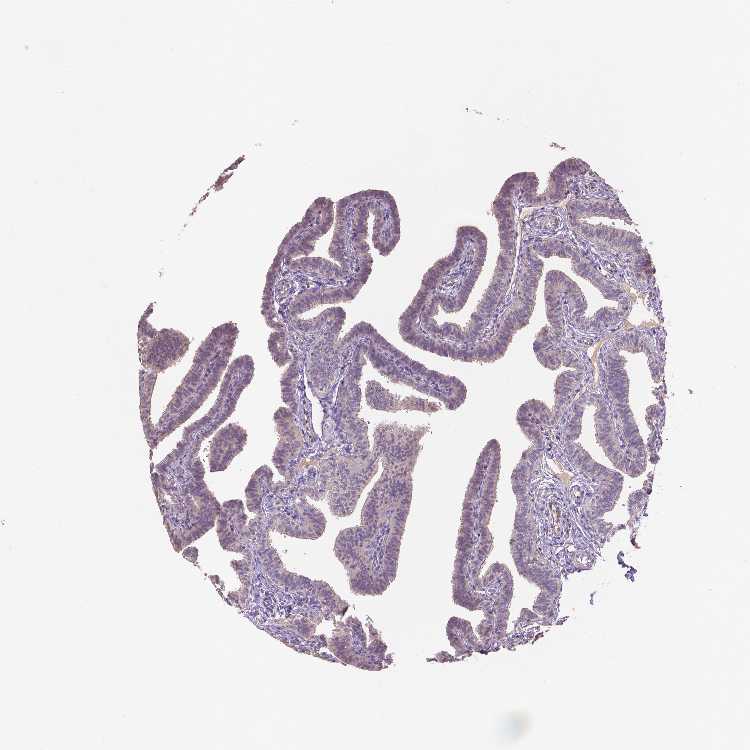

FALLOPIAN TUBE - Antibody stainingi

Antibody staining in the annotated cell types in the current human tissue is reported as not detected, low, medium, or high, based on conventional immunohistochemistry profiling in selected tissues. This score is based on the combination of the staining intensity and fraction of stained cells.

Each image is clickable and will lead to virtual microscopy that enables deeper exploration of all samples and also displays staining intensity scores, fraction scores and subcellular localization as well as patient and tissue information for each sample.

Antibody HPA064219

Glandular cells Low